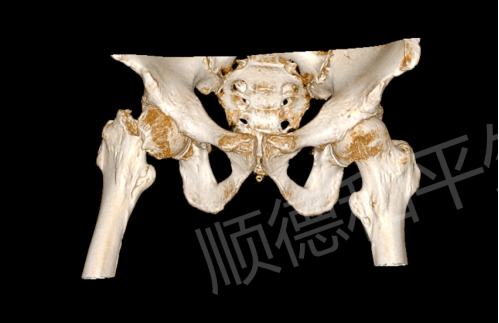

事发当天下午,陈阿姨(化名)在家中不慎摔倒,右侧臀部重重着地,瞬间传来剧烈疼痛,无法站立行走。家人紧急将其送往附近医院检查,X线片提示“右股骨颈骨折(GardenIV型)”,这是股骨颈骨折中较为严重的类型,保守治疗效果差,且极易导致股骨头坏死等后遗症。为寻求更优质的治疗方案,陈阿姨在家人的陪同下转至顺德和平外科医院急诊。

我院急诊医生接诊后,迅速完善相关检查。专科查体显示,陈阿姨右髋关节轻度肿胀,局部压痛及纵向叩击痛明显,髋关节活动严重受限,患肢较健侧短缩2cm,万幸的是远端各趾血运、感觉及活动正常。结合外院影像学资料,“右股骨颈骨折”诊断明确。更棘手的是,陈阿姨年事已高,基础疾病较多,这无疑增加了治疗的复杂性和手术风险。